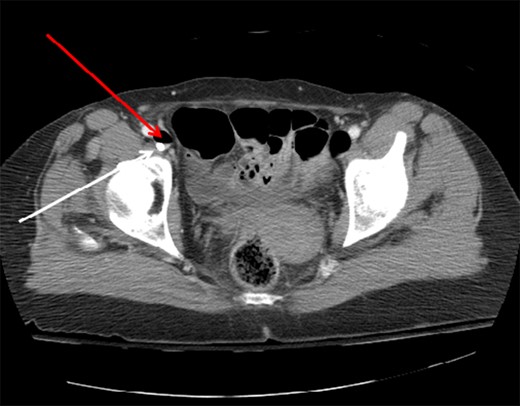

A 66-year-old female patient presented to our level I trauma center after a motor vehicle collision. She sustained multiple injuries including several fractured ribs, hemopneumothorax and a right diaphragmatic rupture. She was hemodynamically normal during her primary and secondary survey, and received a right femoral vein central venous catheter (CVC) for fluid resuscitation. She underwent computed tomography (CT) scan for further diagnostic evaluation and was noted to have the aforementioned injuries and a significant amount of air within the IVC, right iliac and femoral veins (Figs. 1–3). She was immediately placed in Trendelenburg position; a new subclavian CVC was inserted and used to withdraw air. Her right femoral vein introducer was suspected to be the source and was removed. She remained stable with no obvious clinical sequelae and underwent operative repair of her diaphragmatic injury. The patient was discharged on hospital Day 10 with no issues.

Axial CT image of the pelvis demonstrating the CVC (white arrow) with adjacent air (red arrow) in the right external iliac vein.